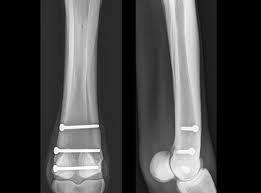

Både hästarna jag såg hade frakturerat metacarpalbenet (skenbenet) på bakben och behövde "skruvas ihop". För att det ska kunna fixas på stående häst så måste såklart vissa kriterier uppfyllas. Frakturen måste sitta på rätt ställe på benet och benbitarna får inte vara dislokerade, d.v.s - de måste sitta ihop rätt.

När allt är preppat så sticker kirurgen in en lång nål vågrätt, precis bakom benet. Man tar sedan röntgenbilder och ser till att nålen som används som riktlinje när man väl ska borra, sitter helt lodrätt (men olika kirurger gör lite olika). Man använder sedan en riktig borr och borrar hål i hästens ben och skruvar in skruvar för att få det att hålla ihop. Beroende på hur lång frakturen är används olika många skuvar. Man mäter också och anpassar längden på skruvarna efter hästens ben. Under operationen tar man sedan röntgenbilder flera ggr för att försäkra sig om att skruvarna sitter rätt.

Nedan ett exempel där man gjort proceduren stående: